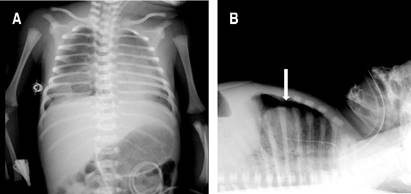

Se procede a realizar UP, como parte del protocolo SAFE,1 observando en la región medial y basal derecha la presencia de neumotórax (Figura 1); mientras que en la región lateral derecha y en el hemitórax izquierdo no se identificaron anormalidades. Cabe señalar que el neumotórax no era visible en la radiografía anteroposterior de tórax, por lo que se solicita radiografía lateral en la cual sí se evidencia el neumotórax anterior (Figura 2).

Figura 2: Radiografía de tórax con equipo portátil. A) Proyección anteroposterior de tórax, sin evidencia de neumotórax. B) Proyección lateral de tórax con imagen de fuga aérea (flecha), correspondiente a neumotórax anterior.